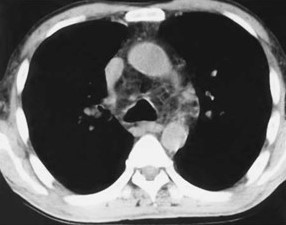

A chest x-ray and CT scan of the chest (Panel A) and a CT scan of the abdomen

and a barium-enema examination of the small bowel (Panel B) are shown below.

Panel A.

The chest x-ray shows widening of the superior mediastinum, aorticopulmonic window, hilar regions, and subcarinal region (left image). The CT scan shows diffuse widening of the mediastinum and hilar regions by low-attenuation fatty tissue (right image).